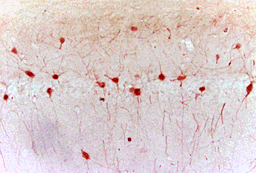

Rabbit polyclonal antibody to NFKB p65 also known as TF65 and RELA whose expression can be detected in the brain and choroid plexus but is highly expressive in the telencephalon and tonsils. It is found in the nucleus after LPS stimulation. NFkB-p65 is a

- Immunofluorescence (Paraffin-Embedded Sections) (IF (P))

- Immunohistochemistry (Frozen Sections) (IHC (Fr))

- Immunohistochemistry (Paraffin-Embedded Sections) (IHC (P))